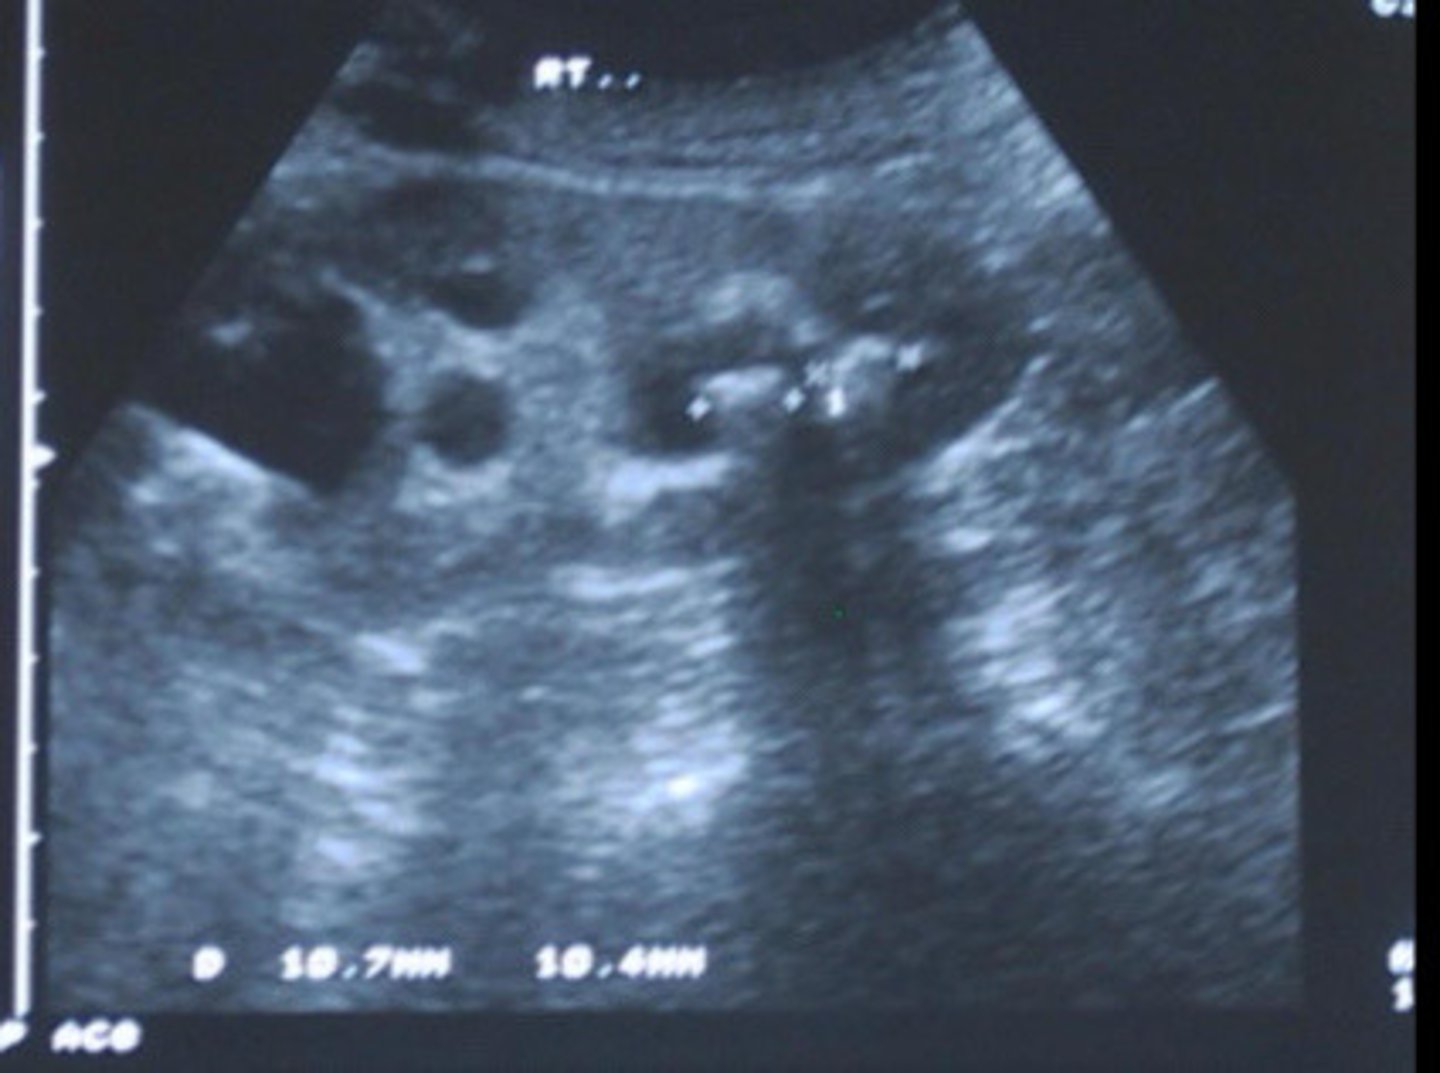

Nephrolithiasis

What does this image show

<p>What does this image show</p>

Echogenic focus or foci with posterior shadowing

Describe the sonographic appearance of nephrolithiasis